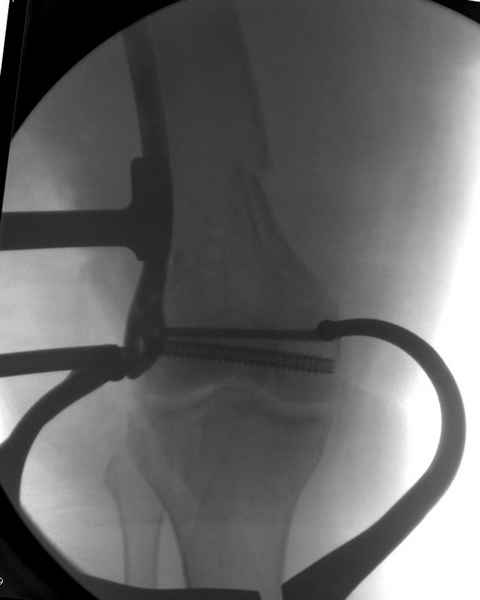

Уважаемые коллеги! От имени Алексея Смирнова всем спасибо за обсуждение. Больной прооперирован. Снимки в приложении.

При наличии различных имплантов, любые варианты: слева (полу) открытым - мининвазивным, а справа закрытым интрамедуллярным методом, его считаем более чем приемлемым для фиксации данных переломов.

Из-за вариабельности установки дистальных шурупов и возможности перкутанного введения проксимально предпочитаем DePuy Polyax, хотя на сегодняшнем маркете множеств вариантов фиксации дистального бедра перкутанном методом.